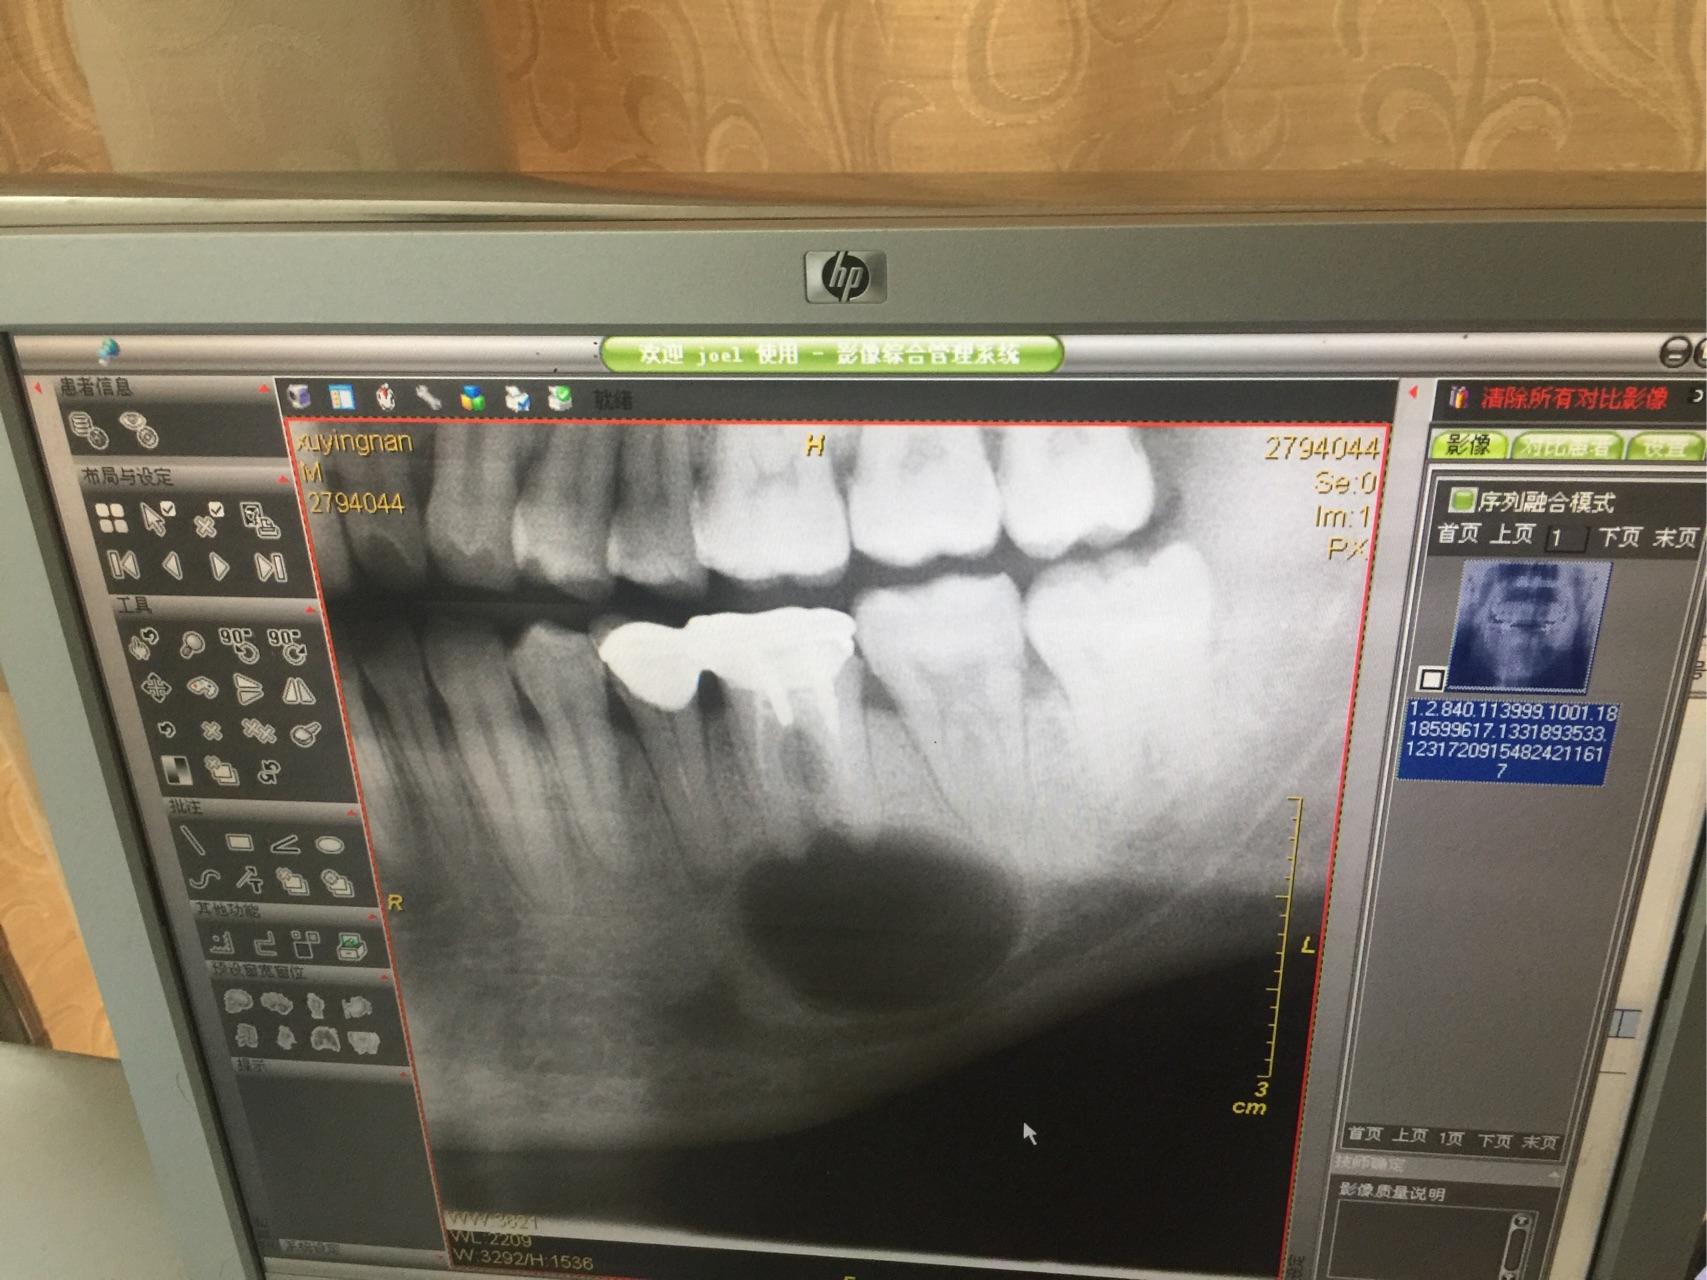

右侧根尖片

图片尺寸640x444